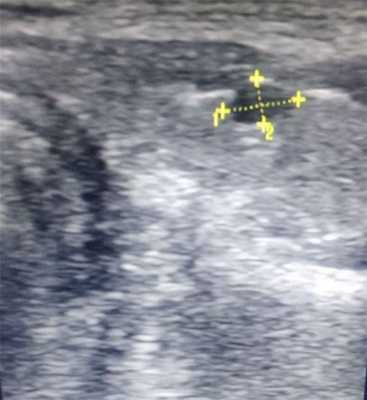

Количество лимфатических узлов в шее особенно велико. Высокочастотный ультразвуковой датчик часто демонстрирует нормальные лимфатические узлы, которые обычно овальные, с максимальным диаметром 8 мм. Корковый слой имеет низкоэхогенную стурктуру, чем более эхогенный мозговой центр лимфоузла. У пожилых людей картина становится все более эхогенной из-за жировой дегенерации, в основном начиная с ворот. Лимфатические узлы пожилых людей труднее обнаружить из-за их низкого контраста с окружающими мягкими тканями. Нормальные сосуды, которые симметрично разветвляются от ворот («хиларная васкуляризация»), могут быть оценены с помощью цветового допплера высокого разрешения.